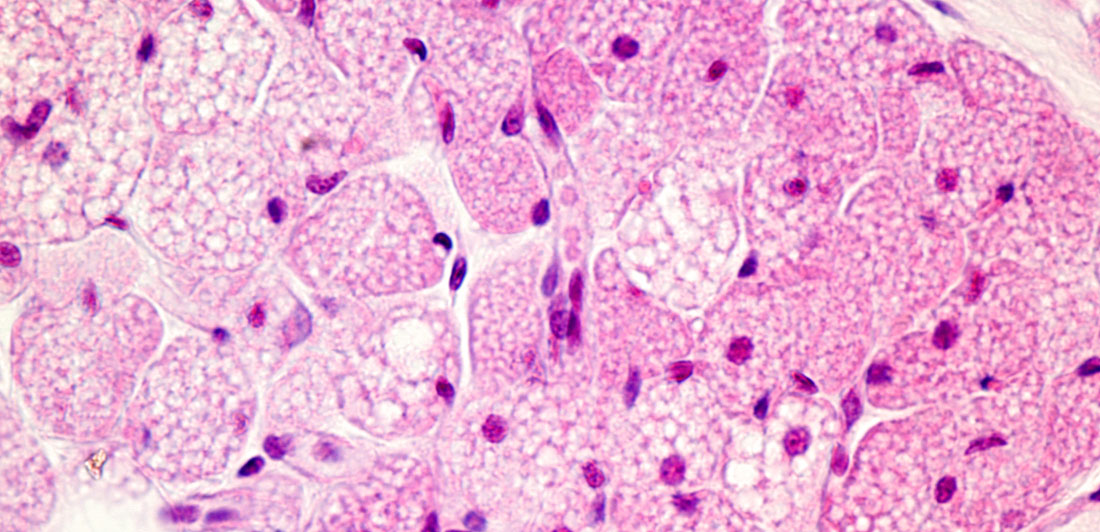

Brown fat is composed of many tiny lipid (fat) droplets as well as many iron-containing mitochondria. It’s usually found in the front and back of the neck and the upper back. The primary purpose is to burn calories, and generating brown fat is a little more complex than white fat.

White fat is composed of a single lipid droplet and has far fewer mitochondria than brown fat. White fat provides the most amount of energy reserve in the body and serves as a thermal insulator and cushion for internal organs. We generate it by consuming too many calories and only using a few calories.